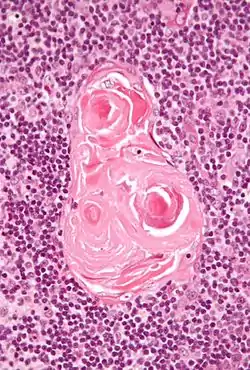

Hassall's corpuscles

Hassall's corpuscles (or thymic corpuscles (bodies)) are structures found in the medulla of the human thymus, formed from eosinophilic type VI epithelial reticular cells arranged concentrically. These concentric corpuscles are composed of a central mass, consisting of one or more granular cells, and of a capsule formed of epithelioid cells. They vary in size with diameters from 20 to more than 100μm, and tend to grow larger with age.[1] They can be spherical or ovoid and their epithelial cells contain keratohyalin and bundles of cytoplasmic fibres.[2] Later studies indicate that Hassall's corpuscles differentiate from medullary thymic epithelial cells after they lose autoimmune regulator (AIRE) expression.[3] This makes them an example of Thymic mimetic cells.[4] They are named for Arthur Hill Hassall, who discovered them in 1846.[5][6]

![]() Micrograph of a thymic corpuscle. H&E stain. | |